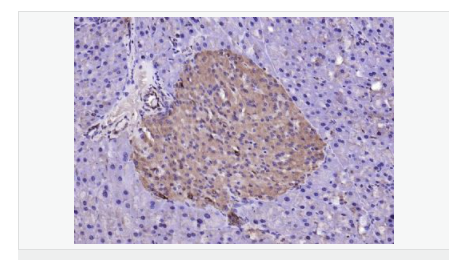

| 英文名稱(chēng) | LSM3 |

| 中文名稱(chēng) | LSM3蛋白抗體 |

| 別 名 | lsm3; LSM3 homolog; LSM3 protein; LSM3_HUMAN; MDS017; SMX4; U6 small nuclear RNA associated (S. cerevisiae); U6 snRNA associated Sm like protein LSm3; U6 snRNA-associated Sm-like protein LSm3; USS2; YLR438C. |

| 研究領(lǐng)域 | 細胞生物 結合蛋白 表觀(guān)遺傳學(xué) |

| 產(chǎn)品應用 | WB=1:500-2000 ELISA=1:5000-10000 IHC-P=1:100-500 IHC-F=1:100-500 ICC=1:100-500 IF=1:100-500 (石蠟切片需做抗原修復) not yet tested in other applications. optimal dilutions/concentrations should be determined by the end user. |

| 細胞定位 | 細胞核 |

| 產(chǎn)品介紹 | Sm-like proteins were identified in a variety of organisms based on sequence homology with the Sm protein family (see SNRPD2; MIM 601061). Sm-like proteins contain the Sm sequence motif, which consists of 2 regions separated by a linker of variable length that folds as a loop. The Sm-like proteins are thought to form a stable heteromer present in tri-snRNP particles, which are important for pre-mRNA splicing.[supplied by OMIM, Apr 2004] Function: Binds specifically to the 3'-terminal U-tract of U6 snRNA. Subcellular Location: Nucleus. Similarity: Belongs to the snRNP Sm proteins family. SWISS: P62310 Gene ID: 27258 Database links: Entrez Gene: 27258 Human Omim: 607283 Human SwissProt: P62310 Human Unigene: 111632 Human Important Note: This product as supplied is intended for research use only, not for use in human, therapeutic or diagnostic applications. |